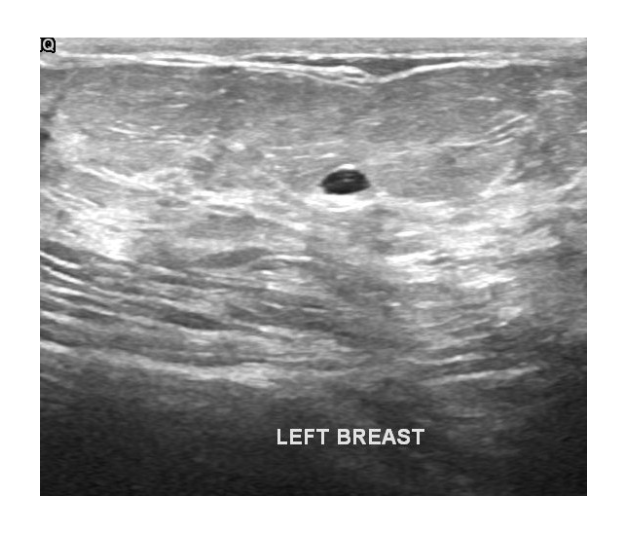

Supports multi-modal inputs including structured indicators, voice, dialogue, and imaging for comprehensive care.

Demo Cases